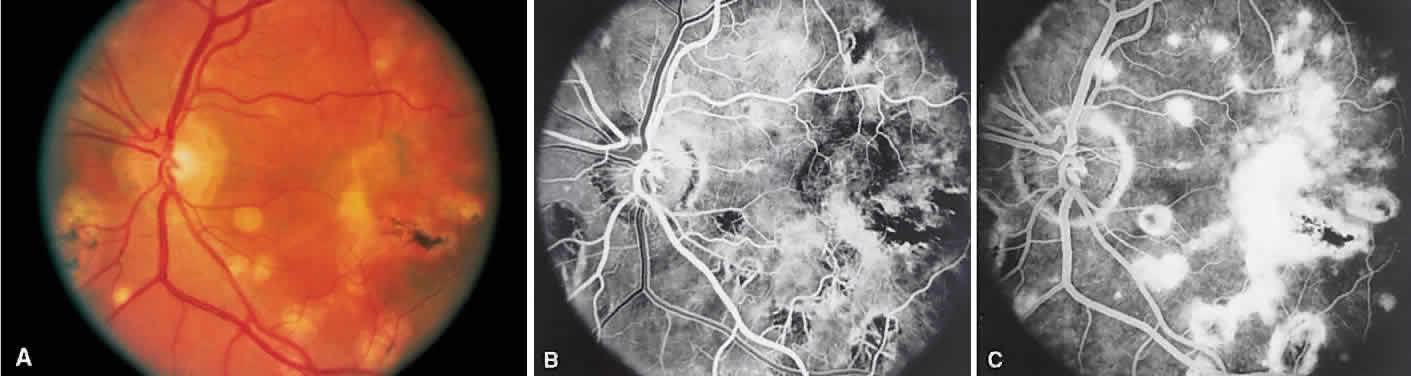

INTERMEDIATE UVEITIS

Intermediate uveitis is also known as pars planitis, peripheral uveitis, and chronic cyclitis. Intermediate uveitis is an inflammatory disease that affects young adults, causing symptoms of photophobia, floaters, and blurry vision. Clinically, mild anterior chamber inflammation, vitreous cells, vitreous snowballs, inflammatory membranes on the pars plana, phlebitis, cystoid macular edema, and, rarely, choroidal and retinal neovascularization are seen.

On fluorescein angiography, there is venular wall staining (Fig. 9),30 hyperfluorescence, and leakage of the peripheral inflammatory membranes.31 Cystoid macular edema often is evident.30 Optic disc, peripheral retinal, and subretinal32–34 neovascularization are rare.

Fig. 9. Intermediate uveitis. A. Red-free photography of the peripheral retina shows sheathing of the retinal venules. B. Fluorescein angiography shows staining of the vessel walls with leakage from the peripheral venules.

BIRDSHOT RETINOCHOROIDOPATHY

Birdshot retinochoroidopathy (also known as vitiliginous chorioretinitis) presents bilaterally, generally in middle-aged women, causing floaters and decreased vision, night blindness, and color blindness. Clinically, there are patches of postequatorial choroidal and retinal pigment epithelial depigmentation (Fig. 10A), vitreous cells, macular and disc edema, and venous sheathing. SRNV frequently is a late sequela. Often central vision may be preserved in at least one eye.

Fig. 10. Birdshot retinochoroidopathy. A. Multiple cream-color deep choroidal lesions. B. Fluorescein angiogram shows leakage of the optic disc and the retinal vasculature. C. Indocyanine green angiography showing areas of hypofluorescence that exceed those observed on fluorescein angiography.

On fluorescein angiography, retinal vessel staining, disc leakage, and cystoid macular edema are found (see Fig. 10B). There often is generalized hypofluorescence of the retinal vessels and increased circulation time.35,36 Surprisingly, the patches of depigmentation may appear normal on angiography, although there can be mild late hyperfluorescence.35,36 Posterior pole choroidal hyperfluorescent lesions that correspond to the areas of depigmentation and SRNV also can be seen.37

On ICG angiography (see Fig. 10C), early and late hypofluorescent patches, exceeding the clinically detectable lesions, with a choroidal vasotropic distribution and relative sparing of the peripapillary area and the central macula, are noted. These findings differentiate this condition from AMPPPE, multifocal choroiditis, and other granulomatous conditions such as sarcoidosis and sympathetic ophthalmia. Rarely, hyperfluorescent spots are noted in the late phases of the angiogram, which correspond ophthalmoscopically to retinal inflammation or obstructive changes.38